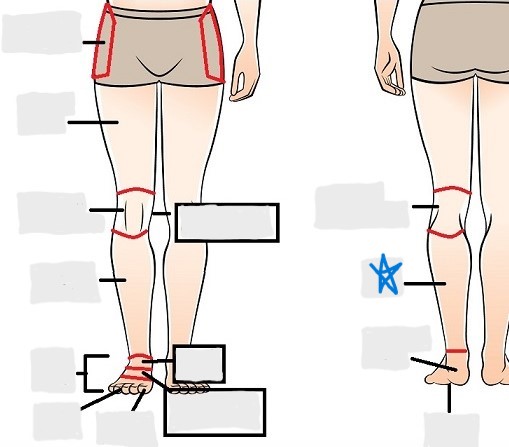

axial

appendicular

coxal

femoral

patellar

popliteal

crural

sural

peroneal

calcaneal

plantar